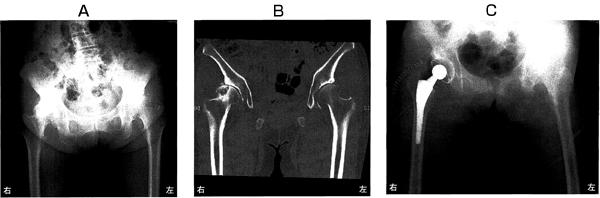

第45回 午前

64歳の女性。10年前から歩行時に右股関節痛を生じ、徐々に増悪して歩行が困難となったため後外側アプローチによる人工股関節置換手術を受けた。術前の股関節部エックス線写真(A)、骨盤部CT(B)および術後の股関節部エックス線写真(C)を別に示す。術前に認められないのはどれか。

1

骨囊胞

2

骨棘形成

3

臼蓋底の肥厚

4

特発性骨壊死

5

関節裂隙狭小化